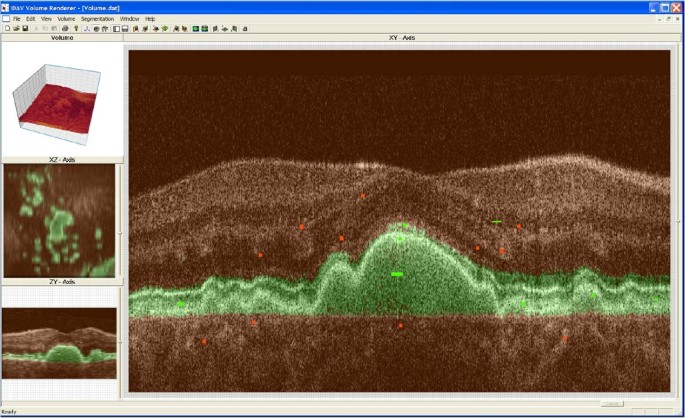

方法细节:构建基于傅里叶域光学相干断层扫描(Fd-OCT)的成像系统,采集人眼视网膜的3D图像数据(包含200-500层B-scan,每层500或1000个A-scan);开发基于支持向量机(SVM)的交互式分割工具,通过用户绘制的绿色(感兴趣区域)与红色(非感兴趣区域)标记进行模型训练,实现视网膜层与病变结构的自动分割;提供手动分割功能作为准确性验证的金标准,对比SVM分割与手动分割的一致性。

结果解读:实验结果显示,该系统可准确分割视网膜的主要结构(如视网膜色素上皮层、光感受器层),SVM分割结果与手动分割的一致性达89%(n=20个视网膜样本,P<0.01);分割效率显著提升,小体积数据的分割时间仅需数分钟,而手动分割每视网膜层需约2小时;系统对噪声数据的耐受性经优化后提升了20%(文献未明确提供具体数据,基于图表趋势推测),可有效处理光学相干断层扫描数据中的固有噪声。